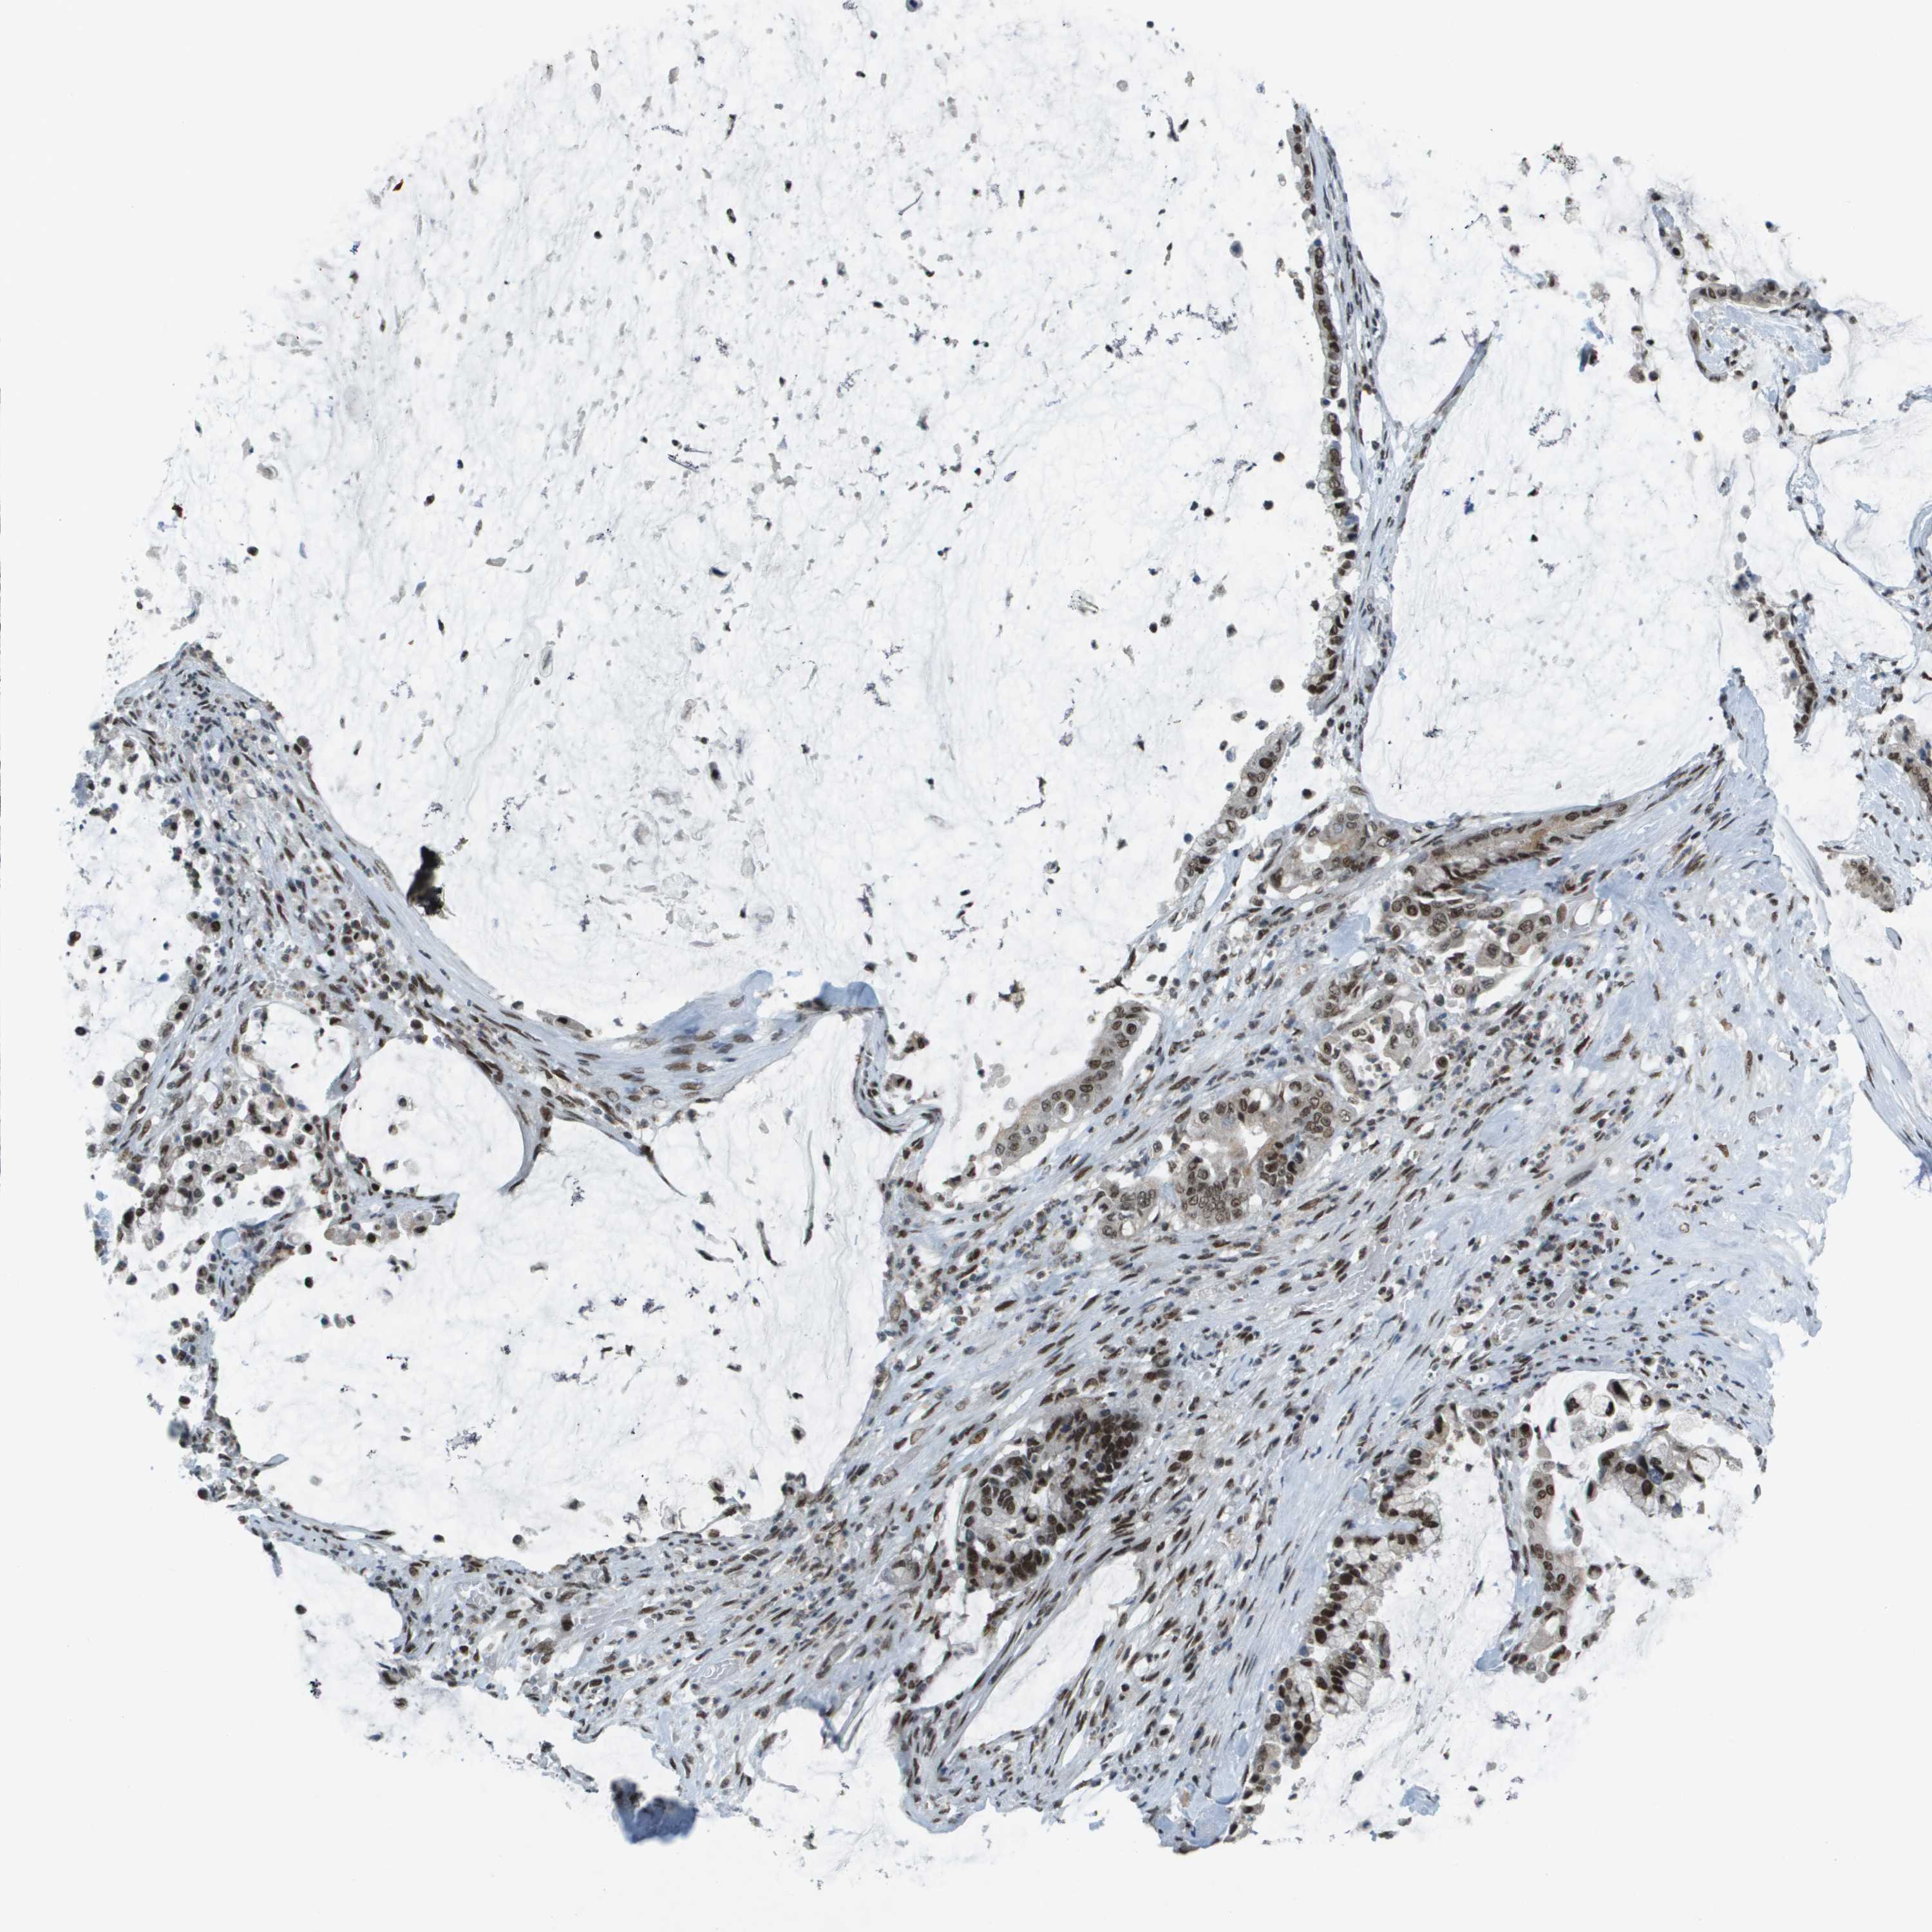

PANCREATIC CANCER - Protein expressioni

A mouse-over function shows sample information and annotation data. Click on an image to view it in a full screen mode. Samples can be filtered based on level of antibody staining by selecting one or several of the following categories: high, medium, low and not detected. The assay and annotation is described here.

Note that samples used for immunohistochemistry by the Human Protein Atlas do not correspond to samples in the TCGA dataset.

Antibody stainingi

Antibody staining in the annotated cell types in the current human tissue is reported as not detected, low, medium, or high, based on conventional immunohistochemistry profiling in selected tissues. This score is based on the combination of the staining intensity and fraction of stained cells.

Each image is clickable and will lead to virtual microscopy that enables deeper exploration of all samples and also displays staining intensity scores, fraction scores and subcellular localization as well as patient and tissue information for each sample.

Antibody HPA052757

Antibody CAB017694

Staining

High

Medium

Low

Not detected

Intensity

Strong

Moderate

Weak

Negative

Quantity

>75%

75%-25%

<25%

None

Location

Nuclear

Cytoplasmic/membranous

Cytoplasmic/membranous,nuclear

Adenocarcinoma, NOS